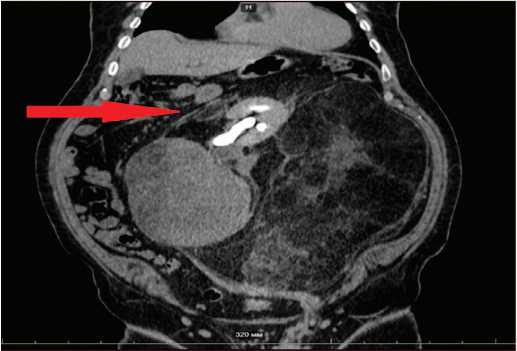

При мультиспиральной компьютерной томографии органов брюшной полости и малого таза с внутривенным контрастированием выявлено объемное новообразование неправильной формы жировой плотности с участками кальцинатов и тканевыми конгломератами, размерами 549×480×339 мм, с плотность в нативной фазе от –102 до +6 ед. HU, которое неравномерно накапливает контрастный препарат: в артериальную фазу – 16 ед. HU, в венозную – 21 ед. HU.

Опухоль компремировала, охватывала и смещала вправо левую почку и левый надпочечник, петли кишечника и поджелудочную железу (рис. 2, 3). В левой половине мошонки определялись множественные варикозно-расширенные вены.

Рис. 2. КТ забрюшинного пространства (ретроперитонеальная опухоль) – коронарная проекция

Fig. 2. CT scan of the retroperitoneal space (retroperitoneal tumor) – coronal projection